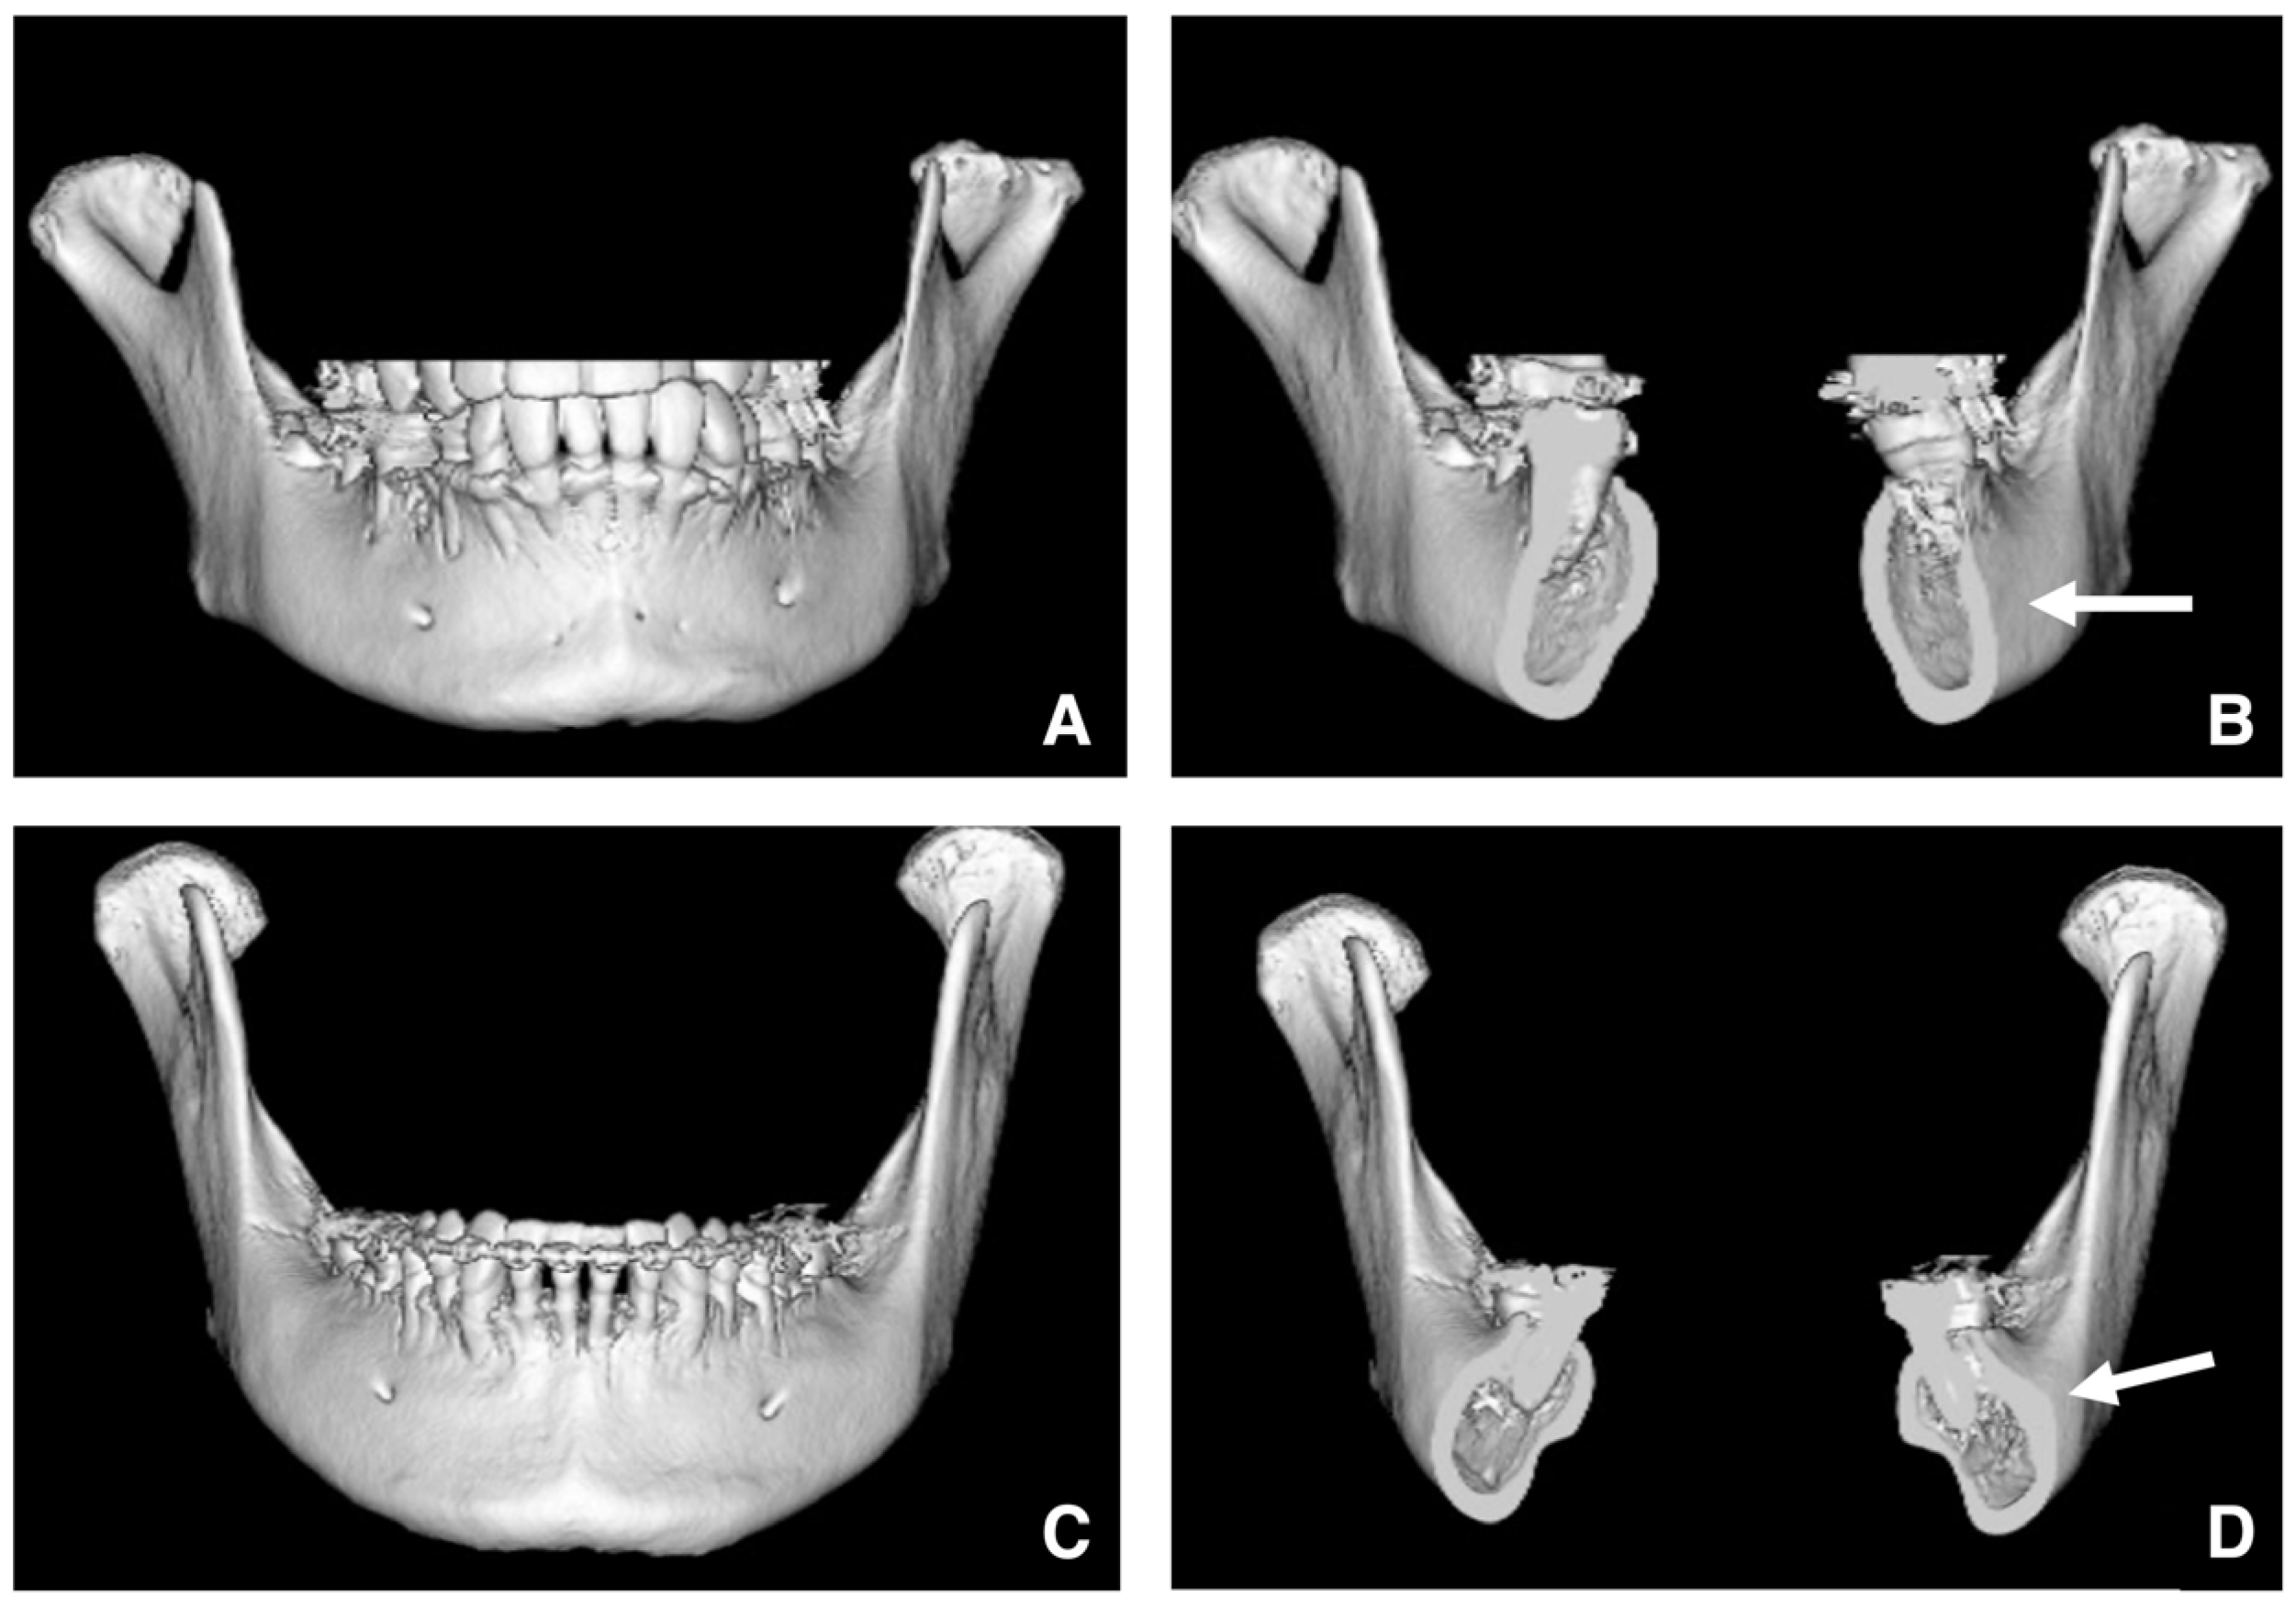

| Setting the osteotomy line 1. Evaluation of the position of the mandibular canal and surrounding bone quality Presence or absence of mandibular canal bifurcation and course of resection site Distance from the buccal wall of the mandibular canal to the buccal cortical bone margin Bone quality around the mandibular canal (CT number) 2. Distance from the mandibular notch to the lingula Whether it is 14 mm or more 3. Morphology of the mandible and variation in cortical bone thickness Cortical bone thickness in the medial osteotomy area and lateral osteotomy area Enhanced safety through improved visibility 1. Medial curvature of the mandibular ramus Mandibular ramus is straight or strong curvature 2. Course of small blood vessels along the bone surface Depression of the buccal-lingual cortical bone from the mandibular fossa to the mandibular ramus region, trabecular bone defect Improved success rates through enhanced postoperative bone integration 1. Degree of interference between bone segments The presence or absence of interference between the proximal and distal bone segments formed during virtual mandibular deformity surgery |